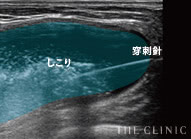

目視しながら確実にしこり除去

ヒアルロン酸豊胸のしこりの多くは、注射器による処置で除去することが可能です。ただし、それはエコーでしこりを目視しながら、正確にアプローチできた場合のみ。触診だけを頼りに治療を行うクリニックもあるようですが、海外では「暗闇の手術」と呼ばれ、とても危険視されている行為です。

一方、THE CLINIC では、乳腺用エコー「エラストグラフィ」で目視しながら、的確にしこりを除去します。最短ルートでしこりを除去するため、体への負担を最小限に抑えることも可能です。

実際のエコー画像

-

溶解液注入

的確にしこりへ穿刺・注入 -

吸引・除去後

しこりの消失を確認 -